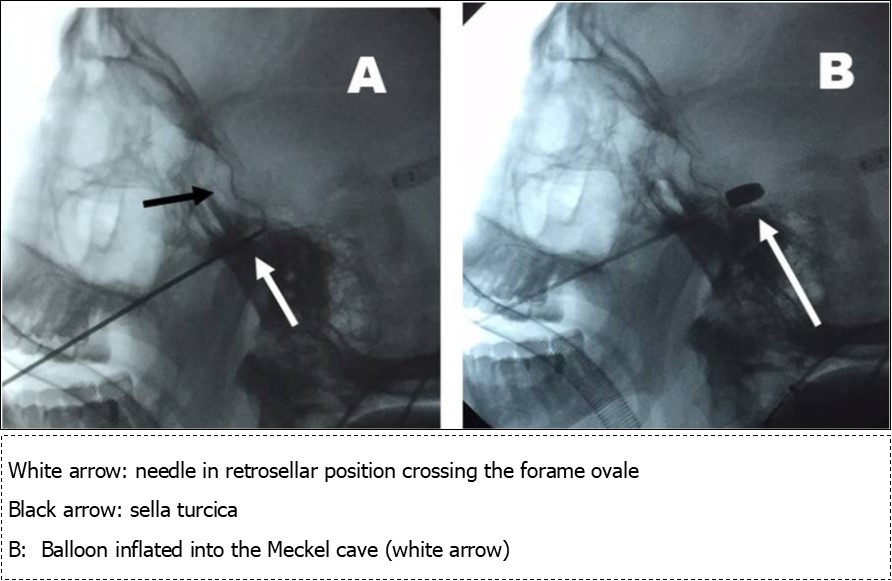

Under fluoroscopic control, in deep sedation without endotracheal intubation, a 4-F balloon catheter with a capacity of 0,7 ml was inserted into the foramen ovale through a 12 gauge teflon catheter guide (Figure 1). The balloon was conducted into the Meckel cave and fluoroscopic control was performed; at this point, the balloon was inflated with iopamidol generating compression of gasserian ganglion (Figure 2); the balloon was kept in situ inflated, compressing the ganglion for about 3-4 minutes. After this time, balloon was deflated but kept into the Meckel cave and sedation was suspended to test the patient: facial sensitivity was explored and procedure was concluded if hypoesthesia was achieved. In 6 patients level of hypoesthesia was too weak, so that patient was sedated again and balloon was inflated and kept is situ for other 6 minutes; suspended sedation, in all patients hypoesthesia was satisfactory and procedure was concluded. Sizes of inflated balloon were: length 18 mm, diameter 6 mm, volume of inflation 0,7 cc.

Figure 1.Procedure of gasserian balloon compression under fluoroscopic control

Figure 2.A: needle positioning into the Meckel cave (retrosellar position)